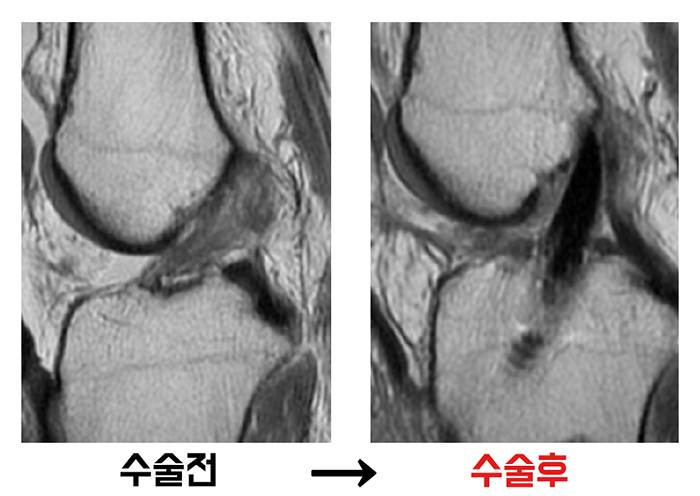

십자인대 재건술십자인대가 완전히 파열되고 불안정성이 심한 경우, 무릎 내의 힘줄을 이식해 인대를 재건하는 수술입니다. 십자인대 시작점과 가까운 무릎 안쪽으로 최소 절개 한 뒤 내시경을 삽입해 병변을 확인합니다. 이후 정강이 뼈와 허벅지 뼈에 통로를 내어 자가인대 또는 자가인대 이식술을 시행하는데, 뼈에 뚫린 터널은 시간이 지나면 자연적으로 재생되어 수술 후 본래의 기능을 회복시킵니다.